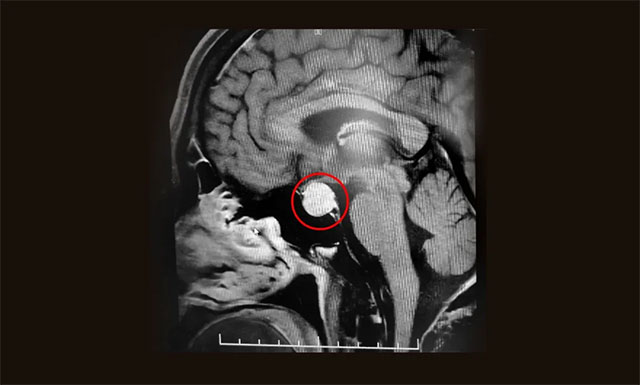

随后,患者进行了头部鞍区MRI平扫+增强,结果显示:蝶窦显著扩大,鞍区见一类圆形肿块,大小约2.0*1.5*1.3cm。垂体柄缩短、左侧偏移;病变向鞍上生长,占据鞍上池,推移视交叉;向下生长,鞍底受压变薄;向鞍旁生长、紧贴海绵窦。

▲ 术前MR影像:垂体大腺瘤,超蝶鞍生长

潘仁龙主任指出,垂体肿瘤向鞍上生长,占据鞍上池,压迫到视神经传导物,使患者视物出现异常。一般1-3cm的大腺瘤或大于3cm的巨大腺瘤,都会引起不同程度的视力问题。